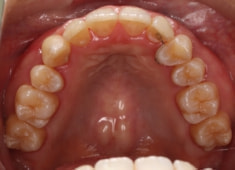

治療前